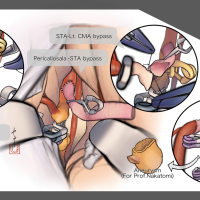

監修:谷川 緑野 / 札幌禎心会病院脳卒中センター

術後イラストシリーズ

監修:太田 仲郎